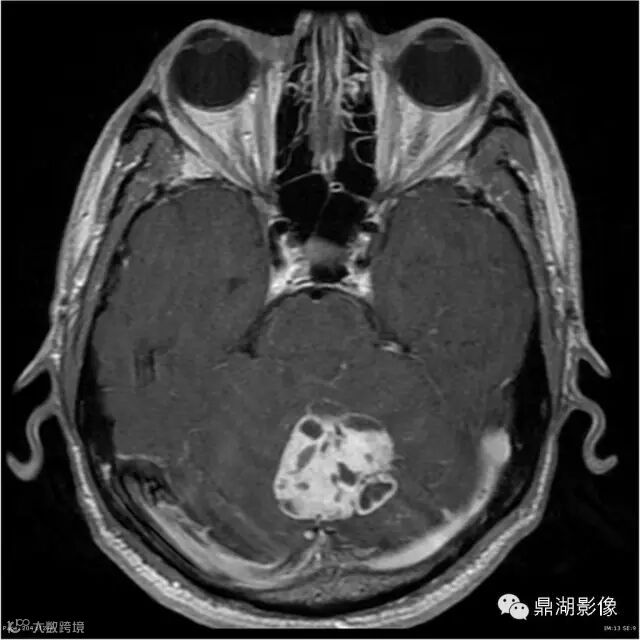

Axial C+

影像:可见一个约43 x 36 x 31mm的从小脑蚓部延伸而来的占位,T1WI、T2WI呈高低混杂信号,病灶周边见流空血管影及水肿带,增强病灶明显强化,中心见无明显坏死区,它紧靠左小脑幕上。第四脑室受压变窄,室管膜水肿,可见脑桥及延脑扁桃体进入枕骨大孔。

3、实质型:肿瘤在T1上呈不均匀等或稍低信号,T2上呈不均匀高信号,FLAIR上,肿瘤呈高信号,增强扫描肿瘤呈明显不均匀强化。实质型肿瘤MRI上在瘤内或瘤周可见呈点状、条状或蚯蚓状的血管流空影,这在诊断实质型血管母细胞瘤上具有一定的价值。

本例为一例实质性血管母细胞瘤。实性血管母细胞瘤CT平扫示病灶呈等或高密度,增强后可见明显强化。MRI平扫通常病灶很不均质,T1呈稍低信号为主的较混杂信号,T2呈等、高信号,DWI通常呈低信号或等信号。文献报道,实性血管母细胞瘤较典型的表现为瘤内及瘤周扩张的流空血管影,瘤周中、重度水肿。因此,小脑半球区的单发肿块伴流空血管影,周围大片水肿以及增强后肿块明显强化"形态规则"边界清楚,此时应将实性血管母细胞瘤考虑在内。